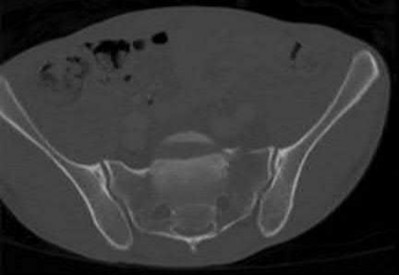

Question 3:

A 55-year-old male undergoes excision of a large cartilaginous tumor of the proximal femur. Molecular analysis of the tumor reveals a mutation in the isocitrate dehydrogenase 1 (IDH1) gene. This mutation is a hallmark of and most frequently associated with which of the following conditions?